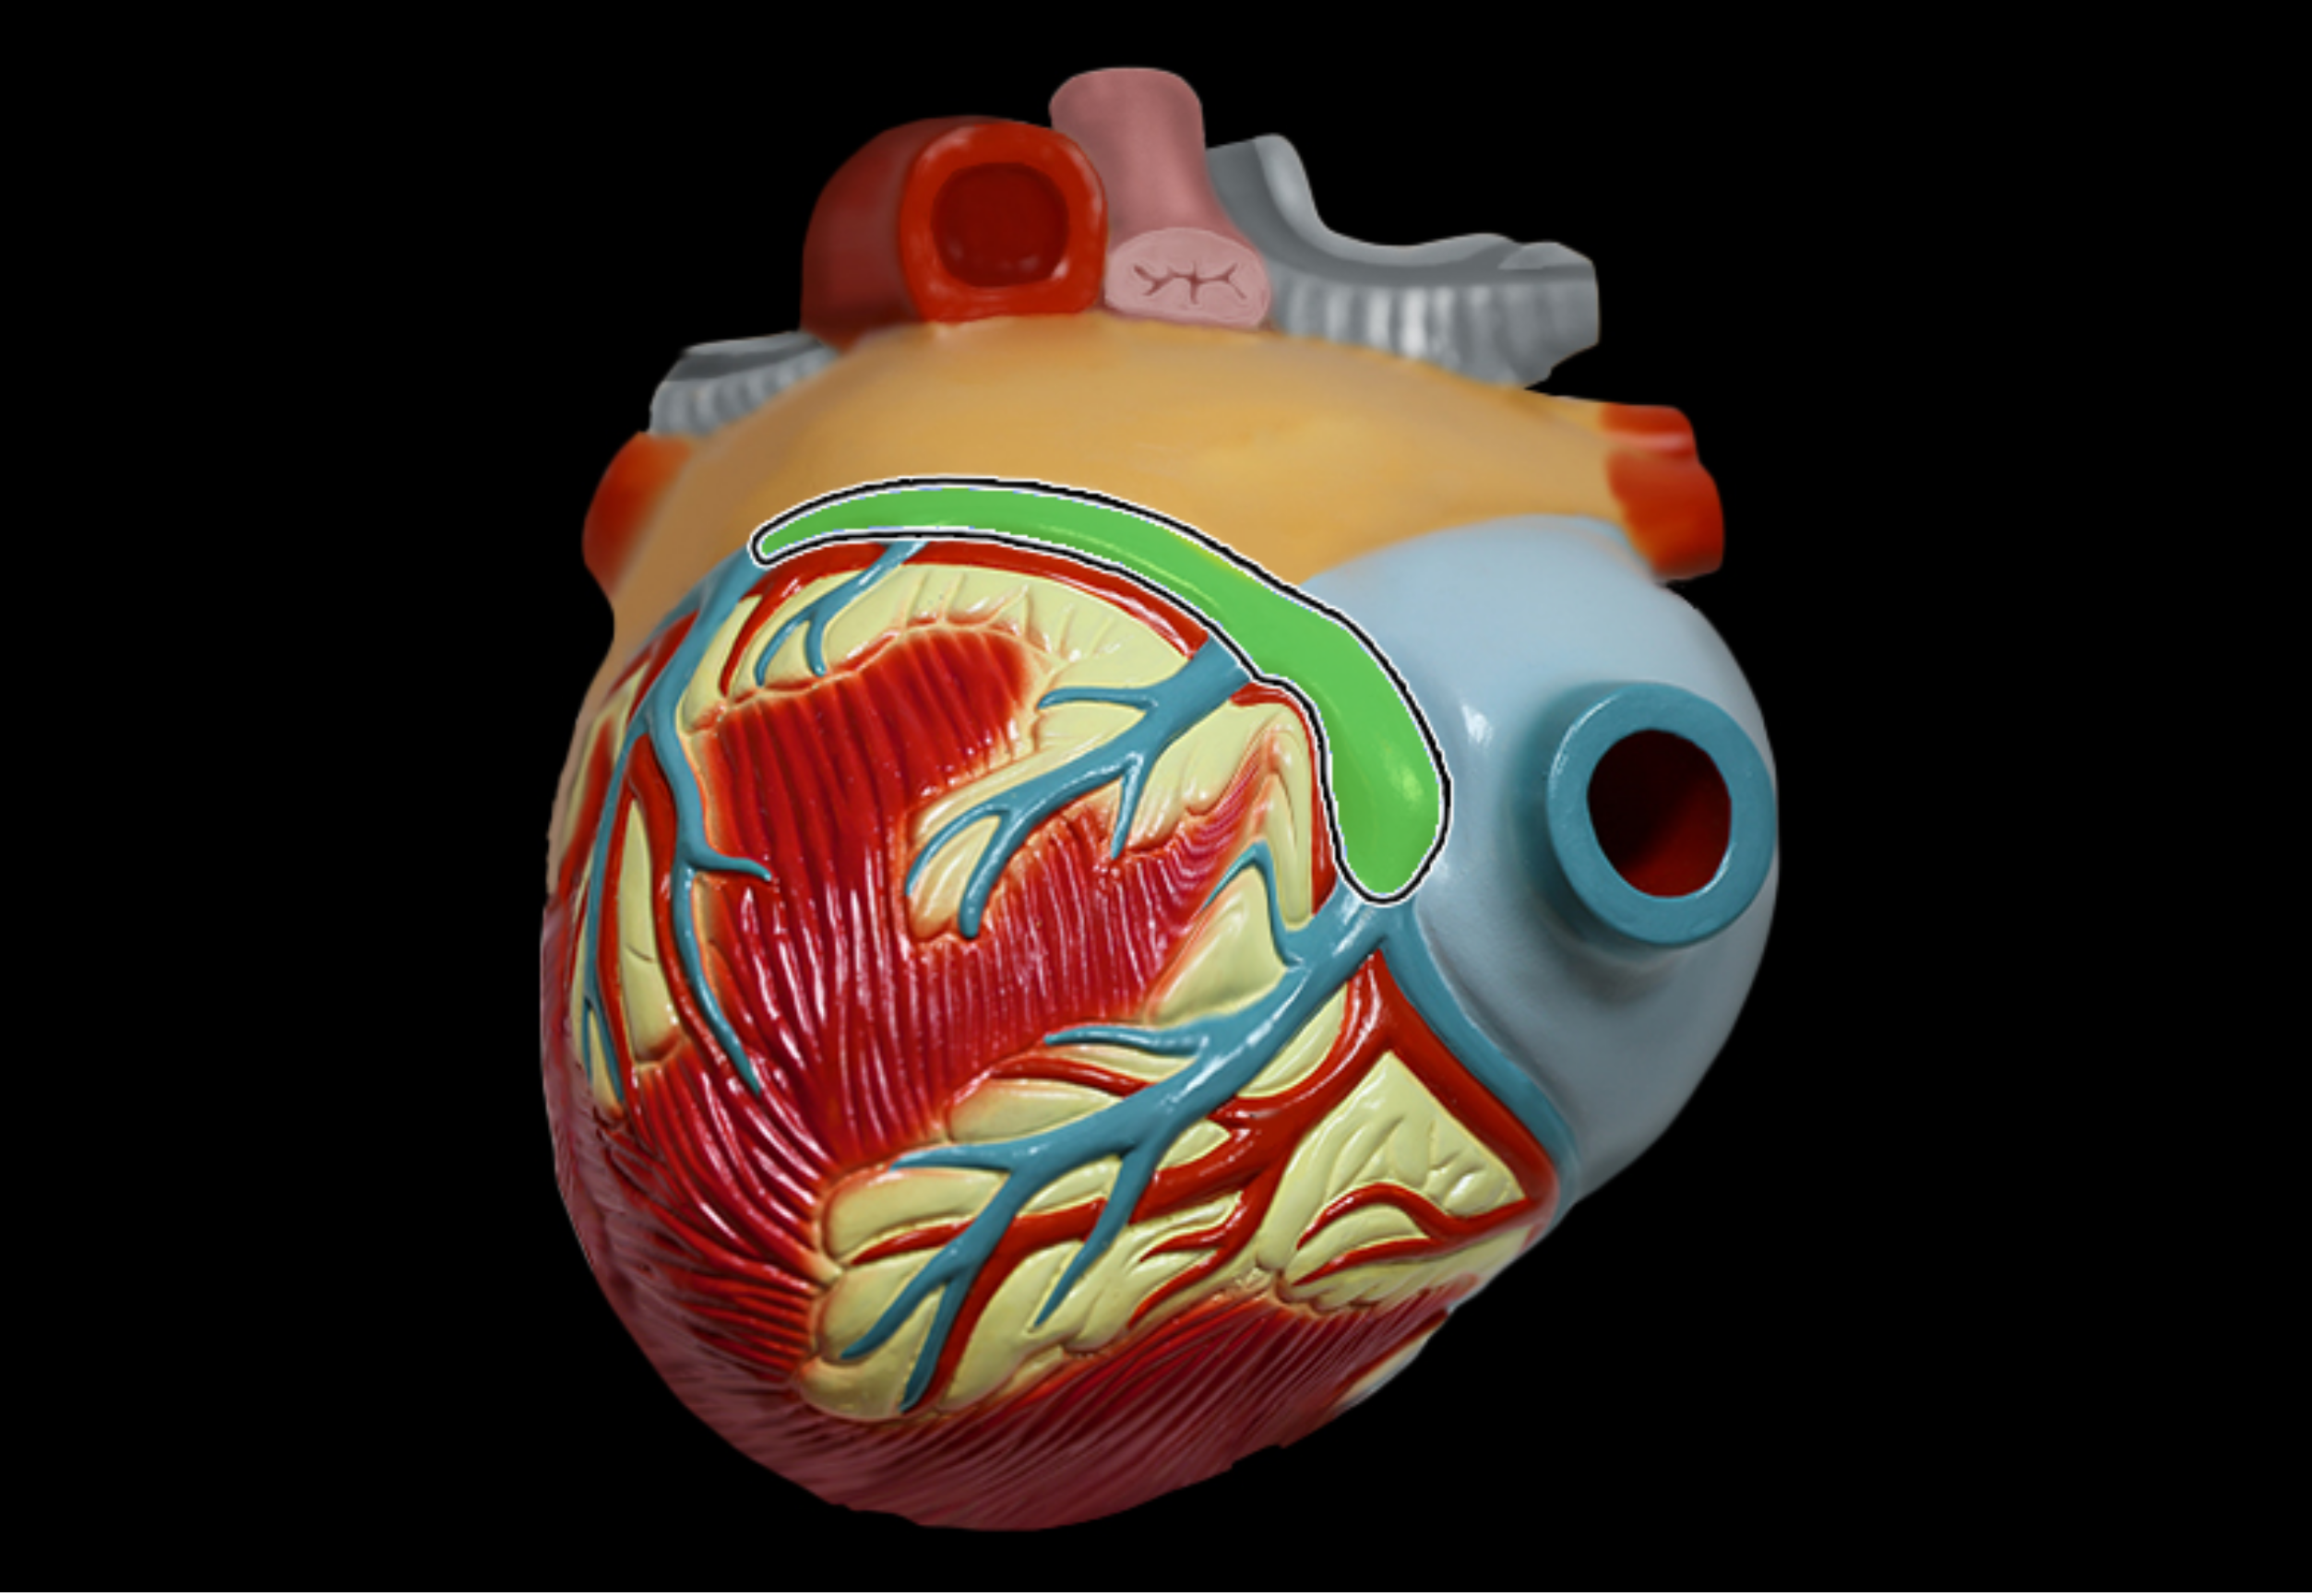

Coronary sinus

Coronary artery (Right)